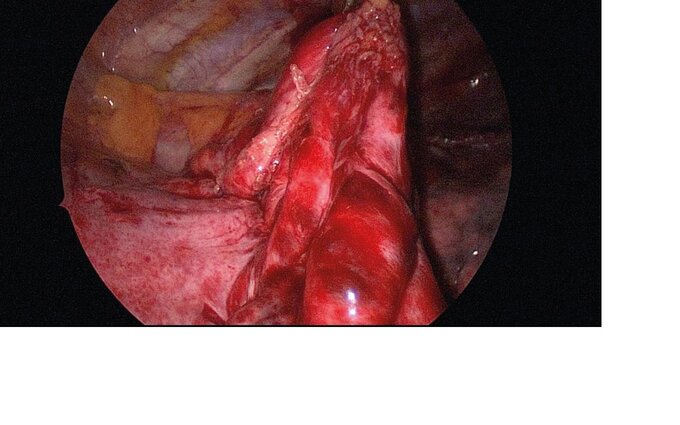

Eine einseitige Zwerchfelllähmung muss nur behandelt werden, wenn der betroffene Patient Atemnot verspürt. Die Therapie der einseitigen Zwerchfelllähmung besteht in einer sogenannten Zwerchfellraffung. Hierbei wird das gelähmte Zwerchfell mit kräftigen Nähten derart gerafft, dass es sich bei der Einatmung nicht mehr in den Brustkorb heben kann. Dadurch kann die Atemarbeit der restlichen Atemmuskulatur wieder besser wirken und es strömt beim Einatmen wieder mehr Luft in die Lunge der betroffenen Seite.

Der Eingriff kann minimal-invasiv durchgeführt werden. Für die Operation ist eine Vollnarkose erforderlich. Vor einer Zwerchfellraffung sollten andere Erkrankungen, die ebenfalls Atemnot verursachen, bestmöglich behandelt werden. Hierzu zählt beispielsweise die Gewichtsreduktion bei übergewichtigen Patienten, oder die medikamentöse Behandlung bei COPD oder Herzinsuffizienz. Da in Abhängigkeit des Ausmaßes der Nervenschädigung der Zwerchfellnerv sich auch wieder erholen kann, empfehlen wir vor einer Zwerchfellraffung einige Monate abzuwarten. Spätestens nach 2 Jahren ist eine Spontanerholung der Zwerchfellfunktion sehr unwahrscheinlich.